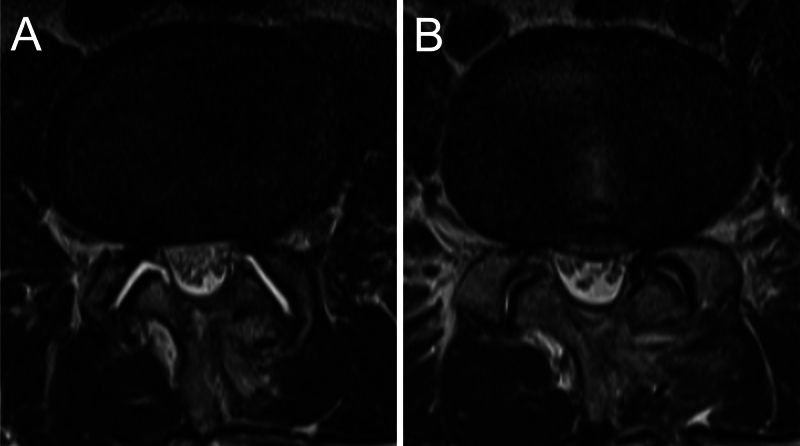

Observations: A 60-year-old man underwent UBE decompression for lumbar canal stenosis and experienced immediate symptom relief. However, 3 weeks postoperatively, he developed acute severe radicular pain, initially presumed to be caused by disc herniation. Despite repeated decompression, his symptoms progressively worsened. MRI findings remained nonspecific, without CSF leakage. Exploratory surgery ultimately revealed herniation of the cauda equina through an occult dural tear. Surgical repair led to rapid symptom relief and complete recovery without neurological deficits.

Abstract Image